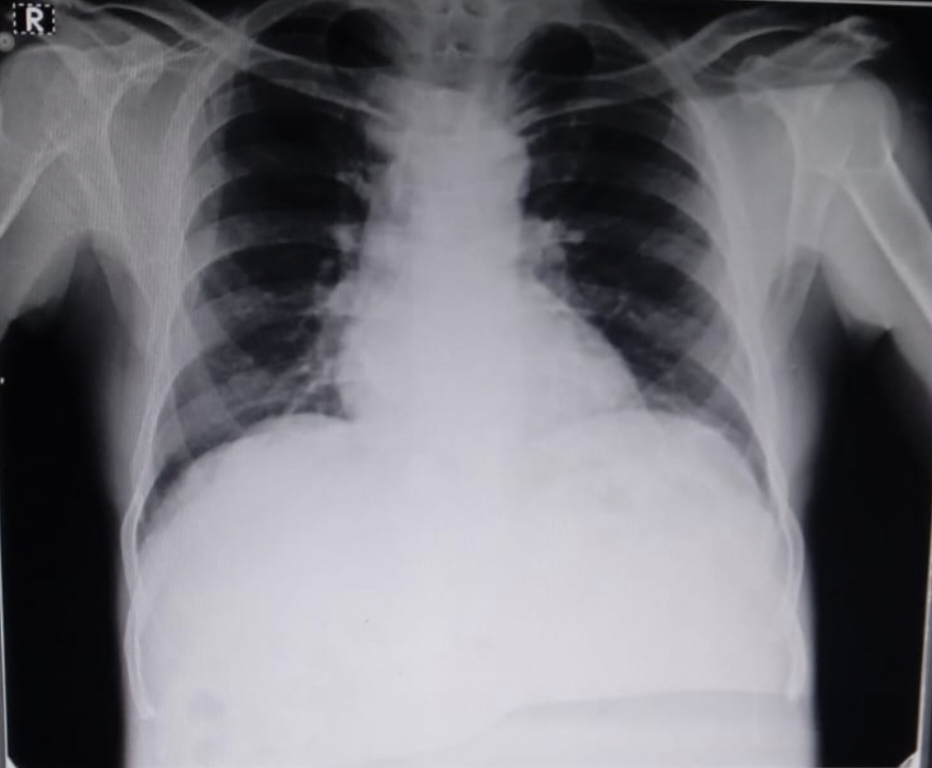

RESPIRATORY SYSTEM

Position of trachea- central

Bilateral air entry, normal vesicular breath sounds are heard.

No added sounds